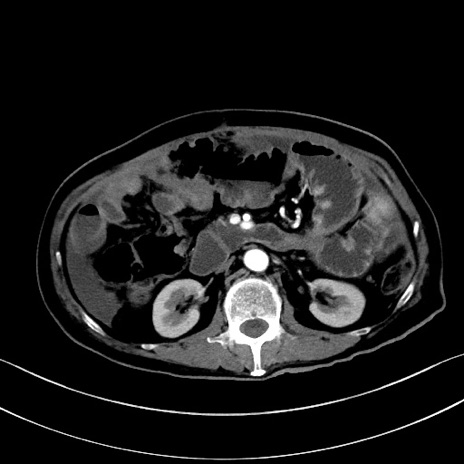

症例28(横断像)

【症例】60歳代男性

【主訴】嘔吐

【現病歴】胃癌にて胃全摘後。食思不振が悪化し、夜中に嘔吐することがある。

【既往歴】胃癌、胃全摘、脾摘、胆摘後

【データ】WBC 5900、CRP 10.56